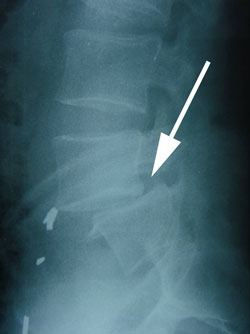

In degenerative spondylolisthesis there is usually some arthritis of the facet joints, the joints between the vertebral bones where motion of the spine takes place. As a vertebra slips forward (white arrow), the disc causes pain because the disc is pain sensitive. The spinal nerve at the spinal level of the slip is also compressed or irritated to cause radiating pain into the buttock whih is often very uncomfortable. It may feel like a toothache or be even more of a boring yet very irritating feeling.